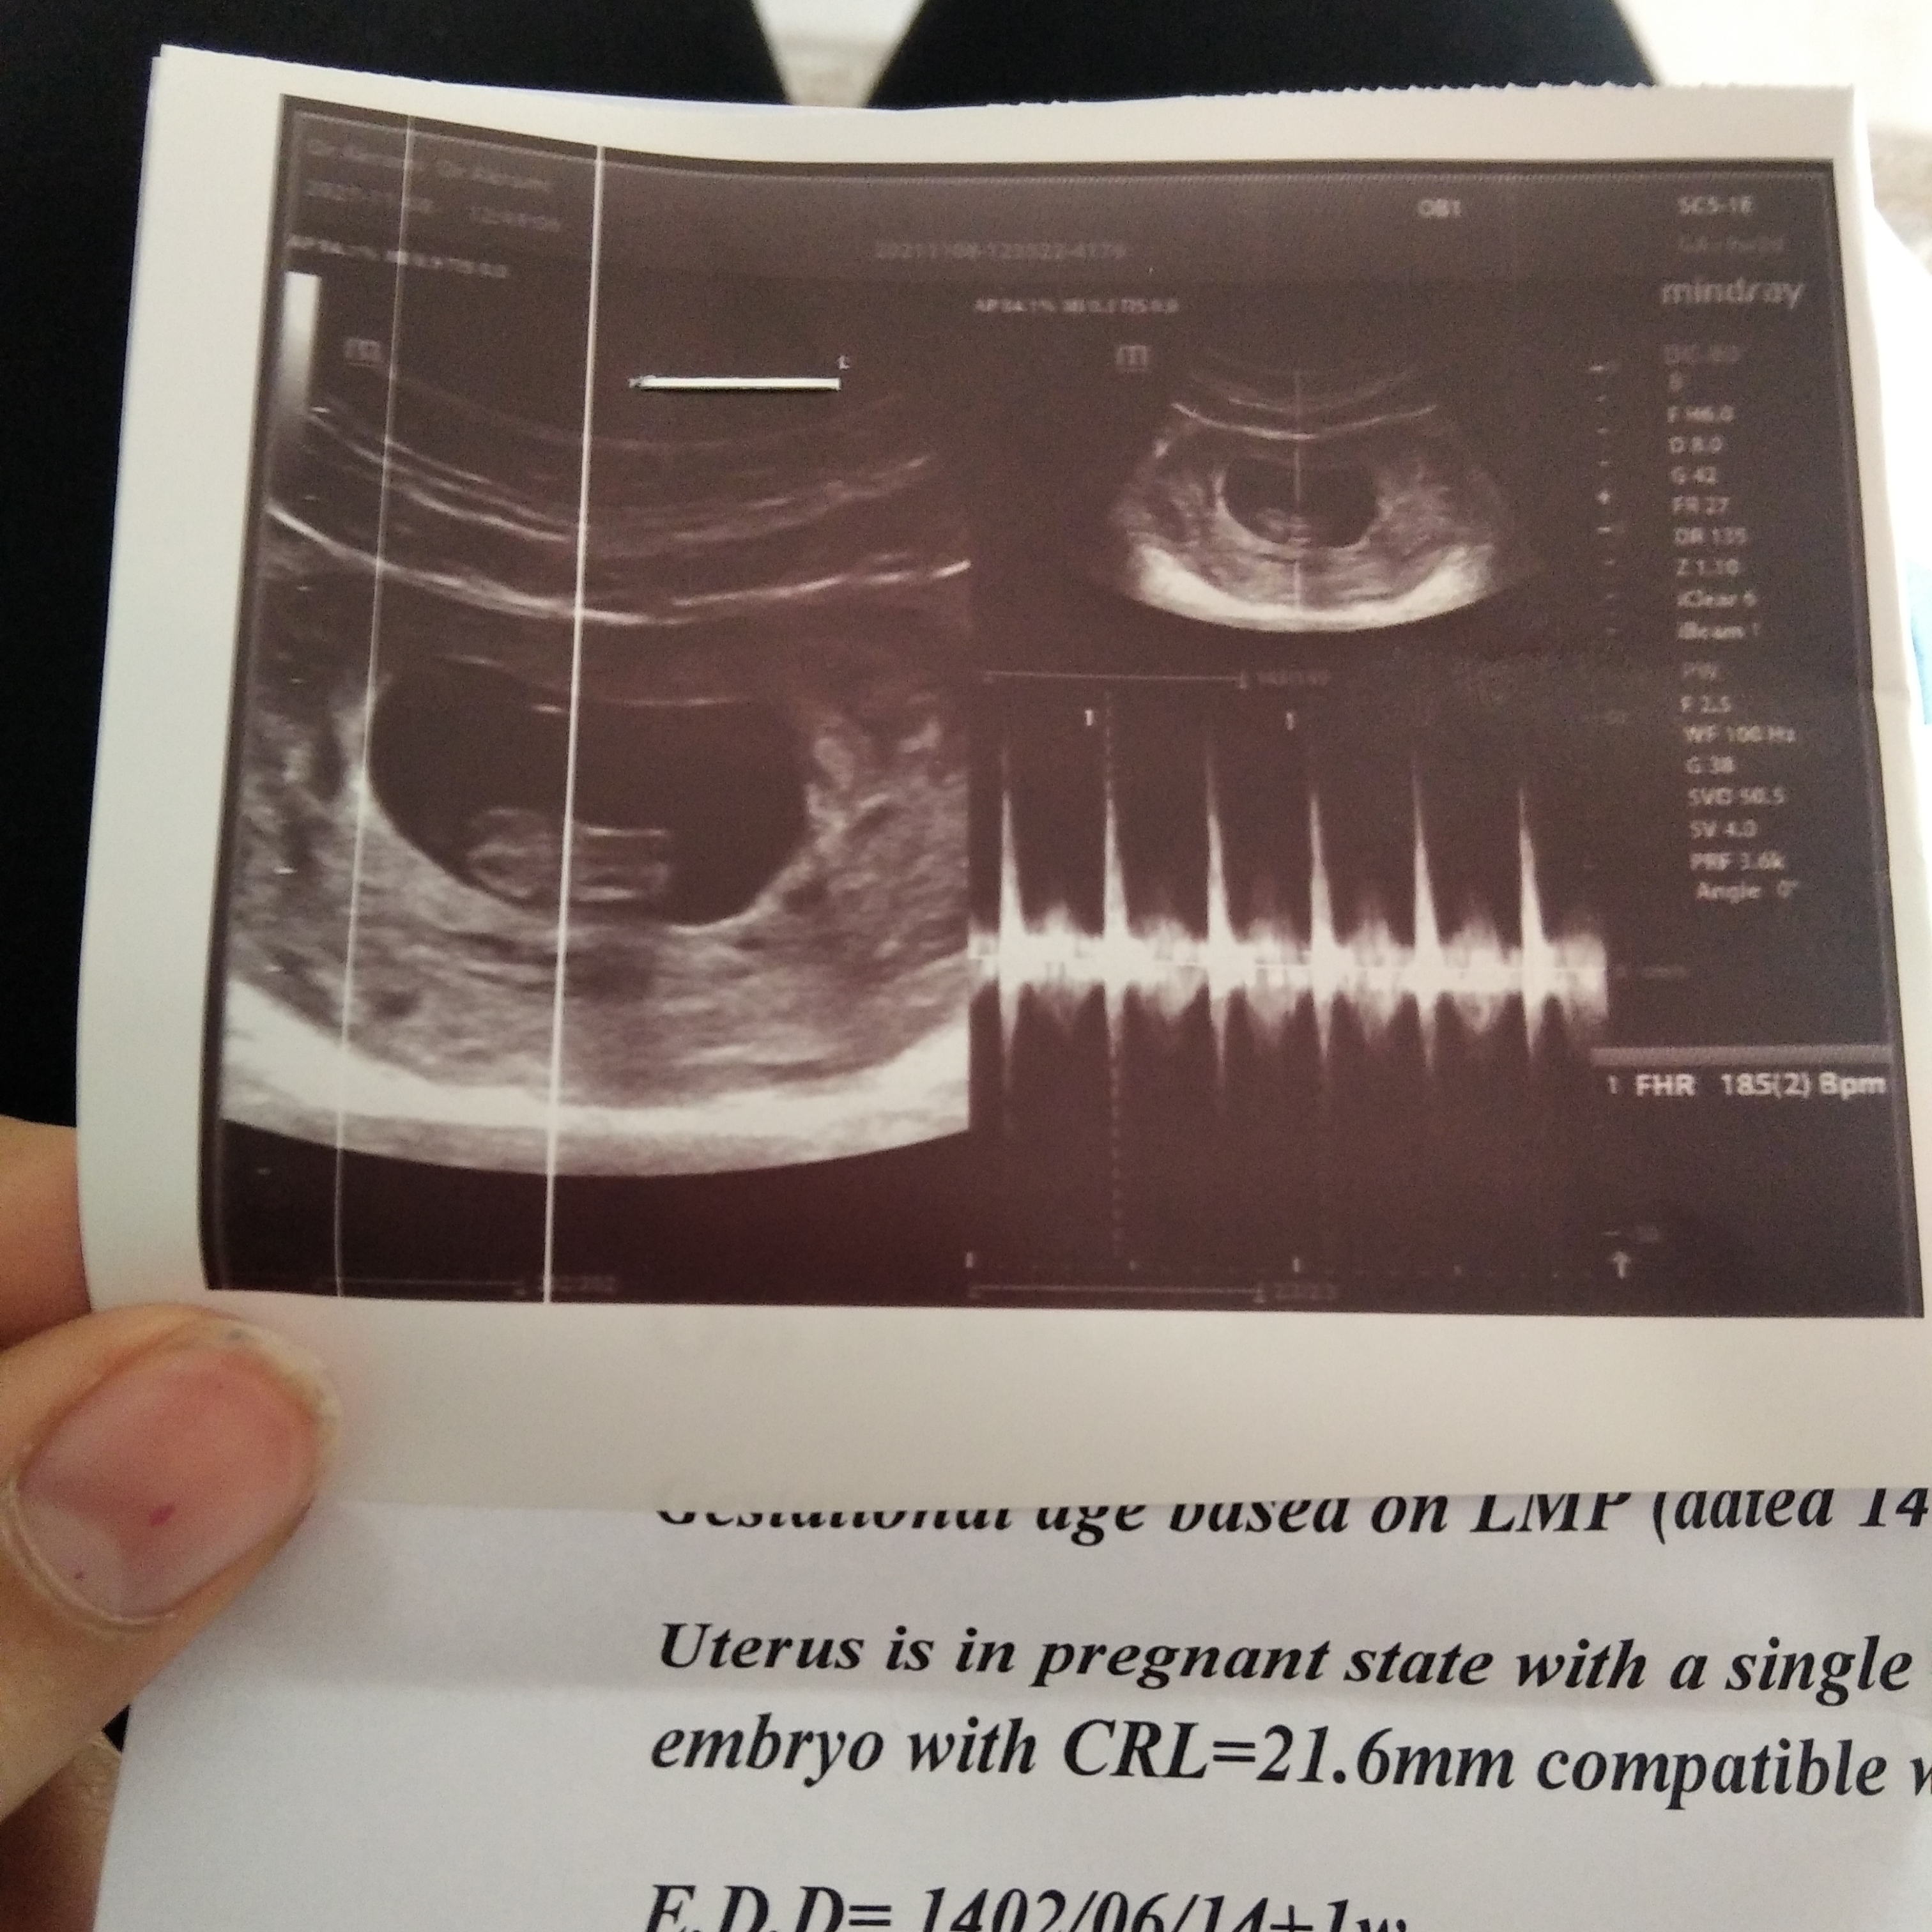

شادییییییییییئ عضویت: 1401/10/29 تعداد پست: 676 ضربان قلب جنین پسر هم تند تره هم یک ذره نامنظمه این ممکنه دختر باشهالبته عزیزم من از روی اطلاعات عمومی میگم